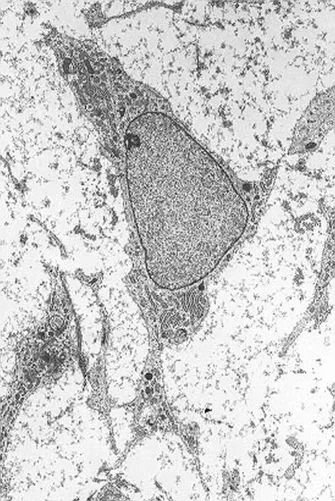

Az őssejteknek számos típusa ismert, a felnőtt szervezetből nyert mezenchimális őssejtek laboratóriumi körülmények között fenntarthatók és szaporíthatók.

A HCEMM kutatóintézet kutatói - Pankotai Tibor és Veréb Zoltán - mezenchimális őssejteket vizsgáltak, amelyek több különféle kötőszövet létrehozásáért felelnek, és amelyeket gyakran alkalmaznak a ma használatos eljárásokban.

A kutatók munkája rámutat arra, hogy a vizsgált őssejtek örökítőanyaga a terápiás felhasználásuk folyamán gyakran károsodik: ebben szerepe van az életkornak, a gyulladt, beteg környezetnek, ahová a sejteket helyezik, és az "átprogramozásnak", ami szükséges ahhoz, hogy az őssejt a kívánt sejttípusokat hozza létre.